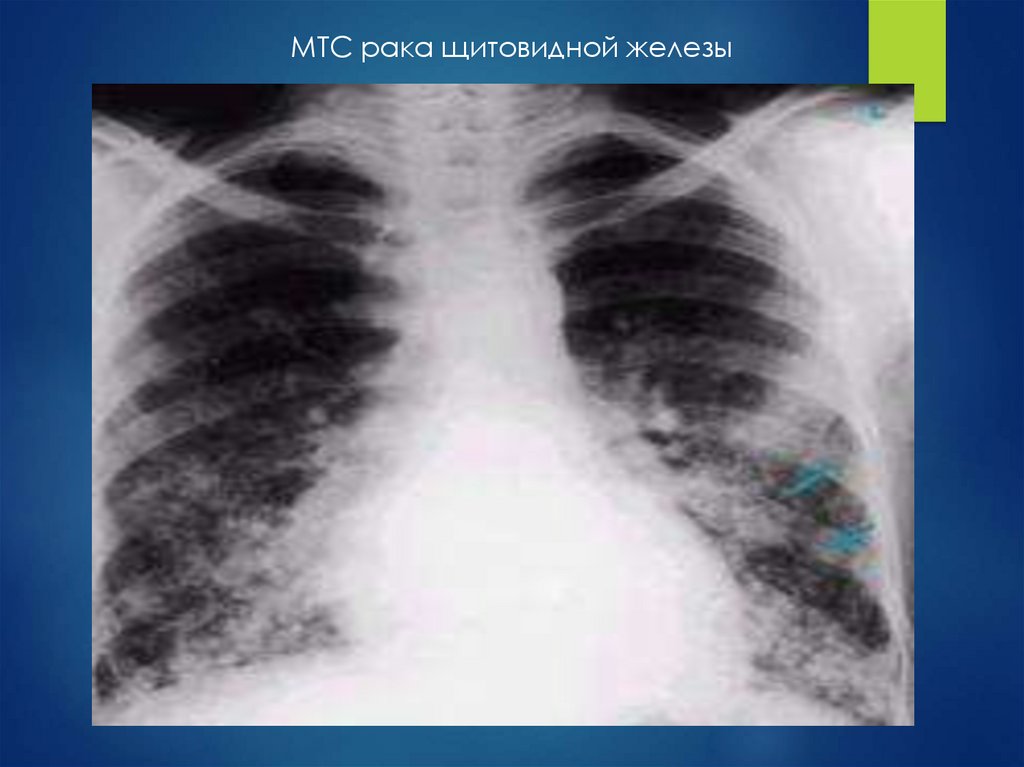

МТС рака щитовидной железы